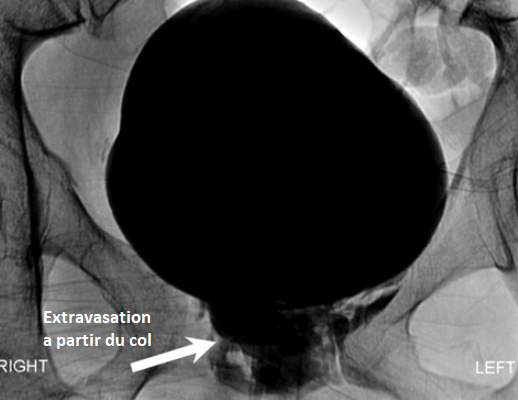

Classification de Goldman

Goldman I

Goldman II

Godlman III

Goldman IV

Goldman IVa